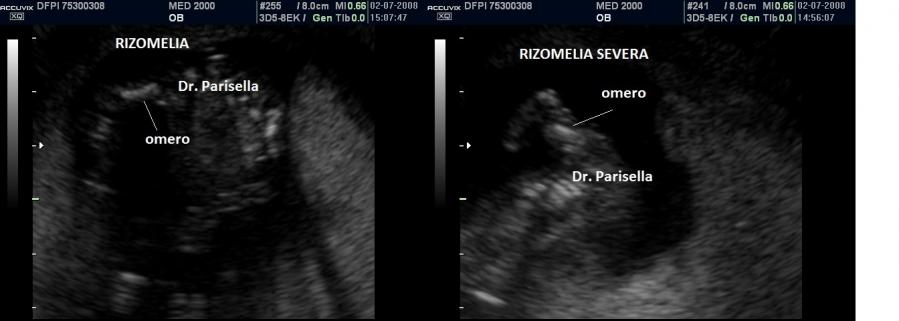

La Displasia Tanatofora tipo 1 è trasmessa con modalità autosomica dominante ed è caratterizzata principalmente da RIZOMELIA SEVERA, FEMORI CORTI (A CORNETTA DI TELEFONO), IPOPLASIA TORACICA SEVERA.

Dal punto di vista ecografico il tratto rizomelico è estremamente ipoplasico, ricurvo e con le metafisi slargate (Femore a Cornetta di Telefono) -  (il riconoscimento del Femore a Cornetta di Telefono rappresenta un segno importantissimo e sufficiente per porre con certezza la diagnosi di Displasia Tanatofora tipo I); vi sono coste corte con ipoplasia toracica e si osserva il classico gradino al passaggio tra torace ipoplasico e addome apparentemente prevalente; vi è in genere macrocrania con bozze frontali prominenti (frontal bossing) e naso a sella. Si associa polidramnios severo.